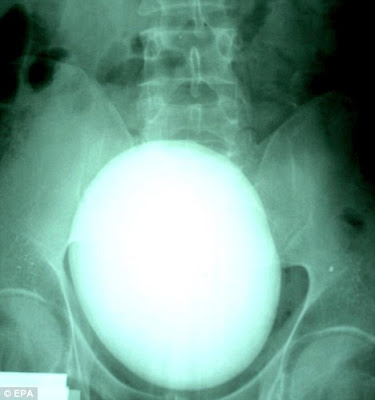

Huge: Patient Sandor Sarkadi has had this 17 centimetre in diameter kidney stone removed

Mr Sardaki was rushed into an operation theatre in the Kenez Gyula Hospital when an X-ray revealed he was carrying around the gigantic lump.

An X-ray earlier in the day revealed the sheer size of Mr Sardaki's stone